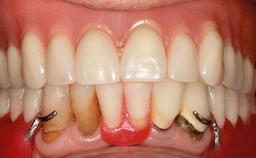

An 83-year-old man presented together with his caregiver at the dental department of the Medical University of Innsbruck, Austria with complaints of swelling in the right maxillary canine area and loss of retention of his 5-years-old mandibular denture. The patient had a significant medical history (20 years) of bipolar affective disorder with moderate depression (F 31.3) and dementia in Alzheimer’s disease (F 00.2). The patient had been in ambulant psychiatric therapy for his depressive illness for the past 20 years. He lived alone and had no children; his sister assisted with daily living. She reported that the patient exhibited compulsive hoarding behavior. In the previous two months, she had noted increasing disorientation and vertigo in the patient. She therefore accompanied him for a medical consultation at the Department of Psychiatry and Psychotherapy of the Medical University of Innsbruck. He was released home after a 6-week inpatient stay.

Infection at Implant Site None Chronic Acute

Soft Tissue Anatomy Intact Defective